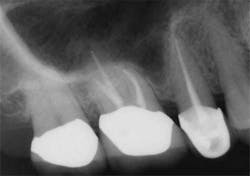

Clinicians rely on a variety of methods to determine working length including, but not limited to, the tactile sensation of feeling the file “pop” through the apex, bleeding on paper points, and radiographs. However, proper use of the EAL, in conjunction with a well-exposed and properly angled preoperative radiograph, will result in the most accurate and reproducible means of determining the true working length. Ideally, this will lead to more predictable and efficient treatment outcomes to maximize both patient comfort and root canal success.On routine six-month recall, the patient was asymptomatic and the access opening was restored. The apical and crestal bone was unremarkable. The follow-up radiograph was taken from different horizontal and vertical angles. Now the fill-in palatal root looks nearly flush with the radiographic apex. A case like this clearly illustrates the limitations of two-dimensional radiographs and the benefits of an EAL for the most accurate working length determination.